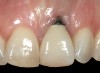

Problem: The implant is placed too facially, and there is significant labial gingival recession, contour change, and mucosal discoloration around the implant, abutment, and crown (Figure 3 and Figure 4). The implant attachment apparatus is intact and healthy, but the patient has a thin periodontal phenotype.

The following case report provides an example of this case scenario: A 28-year-old white female patient presented with her maxillary right lateral incisor significantly longer than the contralateral tooth following restoration of an existing crown that was 10 years old (Figure 3). The patient was dissatisfied with the esthetic appearance of the restoration due to the increased length, recession of the gingival tissues, and discoloration of the surrounding mucosa (Figure 4). Similar to case scenario No. 1, the first step in treatment was to decoronate the healthy implant by placing a flat surgical cover screw and employing a provisional resin-bonded-retained (RBR) prosthesis as a transitional fixed restoration (Figure 5 and Figure 6). The gingival augmentation in situ was allowed to take place for 2 to 3 weeks and was evaluated after that time (Figure 7).

Fig 5. A surgical cover screw was placed onto the implant in order to achieve gingival augmentation in situ prior to a secondary soft-tissue procedure.

Fig 6. A transitional resin-bonded-retained dental prosthesis was used to replace tooth No. 7.